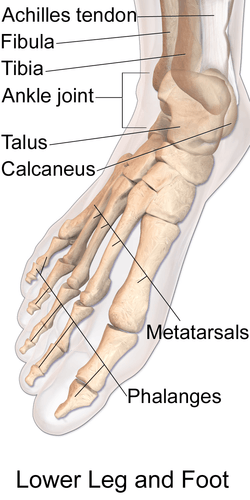

The talus bone (/ˈteɪləs/; Latin for ankle[1]), astragalus /əˈstræɡələs/, or ankle bone is one of the group of foot bones known as the tarsus. The tarsus forms the lower part of the ankle joint through its articulations with the lateral and medial malleoli of the two bones of the lower leg, the tibia and fibula. Within the tarsus, it articulates with the calcaneus below and navicular in front within the talocalcaneonavicular joint. Through these articulations, it transmits the entire weight of the body to the foot.[2]

The talus bone of the ankle joint connects the leg to the foot.